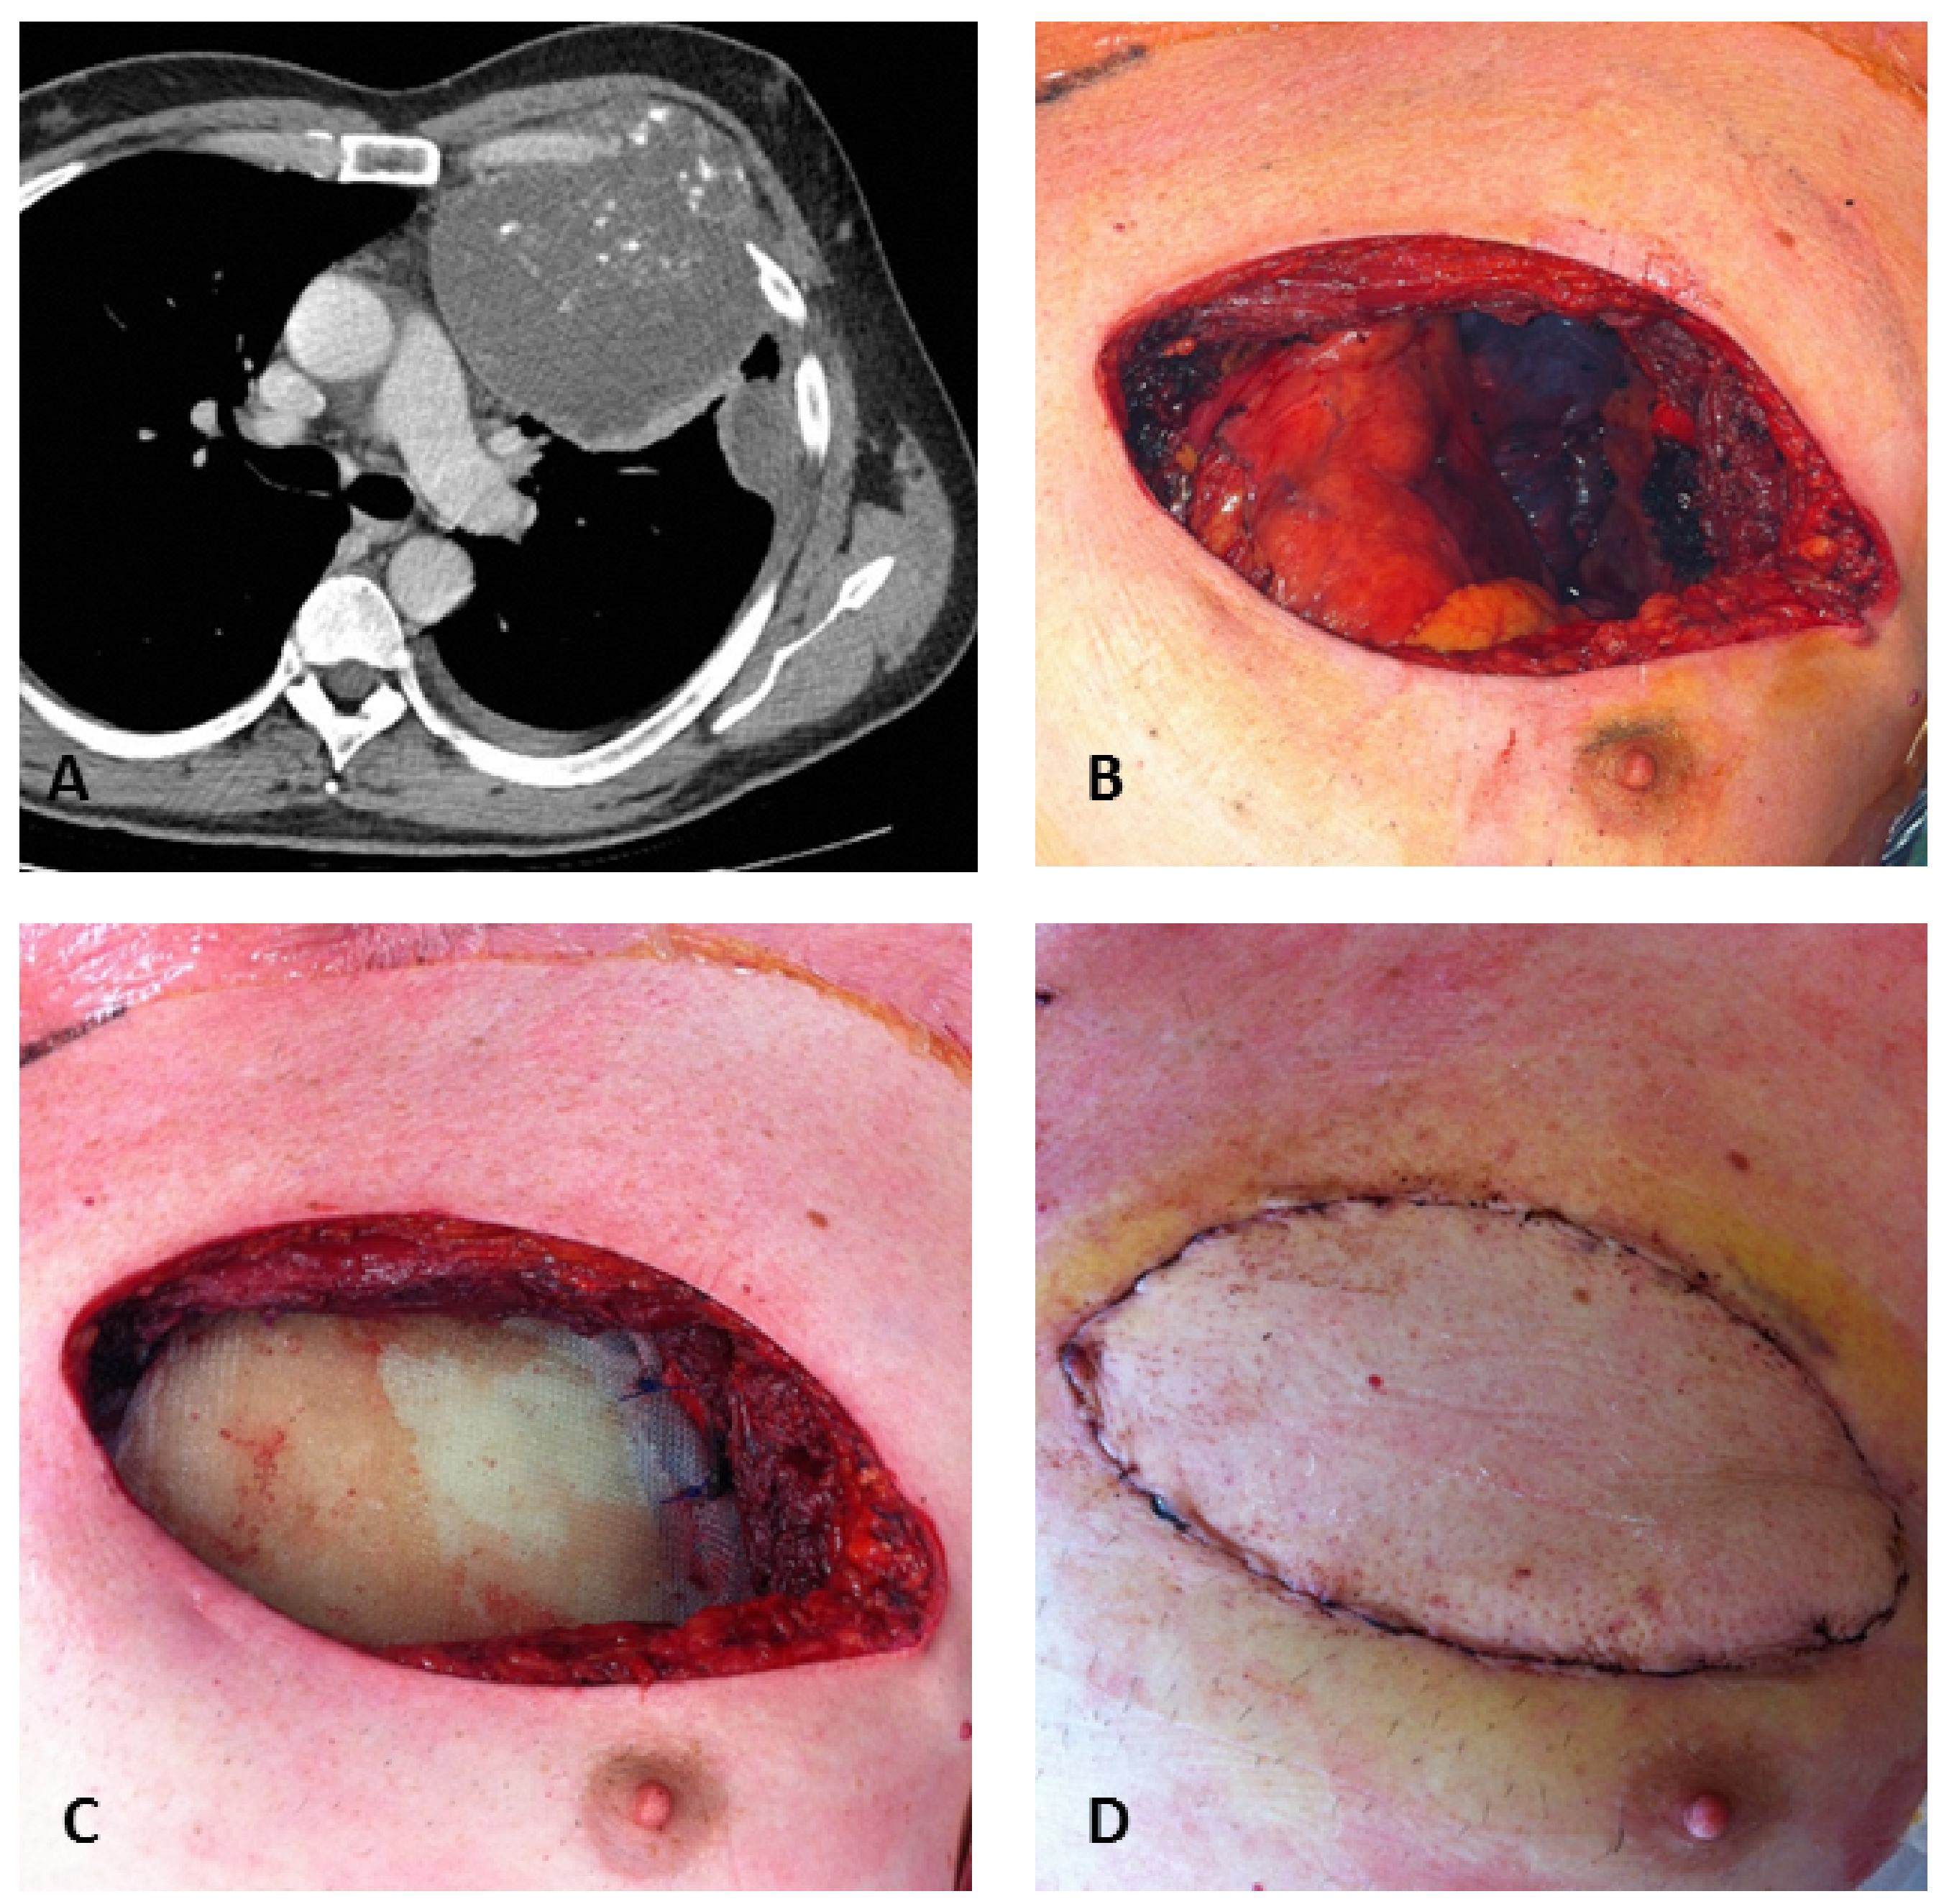

| Tumor location | Costochondral junction | 9/11 (82%) | 10/15 (67%) | 0.804 | 19/26 (73%) |

| Sternum | 2/11 (18%) | 4/15 (27%) | 6/26 (23%) | ||

| Tumor size | Mean in mm (range) | 56 (31–151) | 57 (20–127) | 0.435 | 57 (20–151) |

| Median in mm (range) | 40 (31–151) | 46 (20–127) | 45 (20–151) | ||

| Character | Lytic only | 0/11 (0%) | 3/15 (20%) | 0.238 | 3/26 (12%) |

| mixed | 11/11 (100%) | 12/15 (80%) | 23/26 (88%) | ||

| Fracture | No | 9/ 11(82%) | 15/15(100%) | 0.169 | 24/26 (92%) |

| Yes | 2/11 (18%) | 0/15 (0%) | 2/26 (8%) | ||

| Soft tissue mass | No | 3/11(27%) | 1/15 (7%) | 0.279 | 4/26 (15%) |

| Yes | 8/11(73%) | 14/15 (93%) | 22/26 (85%) |